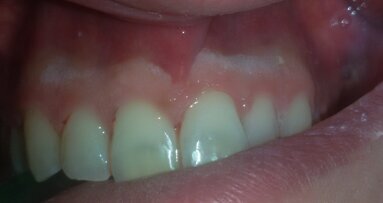

Acquisita l’impronta digitale postoperatoria, questa è stata inviata allo stesso laboratorio specializzato (IDI Makers) per la fabbricazione delle protesi provvisorie. Il decorso post-operatorio è stato privo di eventi significativi. Al termine dell’intervento, non sono state applicate viti di guarigione. Ciò ha favorito il trofismo dei tessuti e ha permesso di ottenere un’ottimale coesistenza senza interferenze degli impianti con i provvisori applicati all’apparecchio ortodontico. La sutura è stata rimossa a 10 giorni dall’intervento. La paziente è stata poi sottoposta a controlli postoperatori di rito fino ad arrivare al momento della finalizzazione protesica. È stata quindi sottoposta a profilassi antibiotica27, 28 e anestesia per effettuare delle modeste incisioni che non interessassero il connettivo profondo al fine del posizionamento delle protesi provvisorie. Queste sono state montate su IDI Base B1ONE con ingaggio senza spalla e con allestimento di un ideale profilo di emergenza finalizzato a un’ottimale guarigione dei tessuti molli perimplantari.

L’apparecchio ortodontico non è stato rimosso per non precludersi la possibilità di effettuare un trimming finale degli spazi protesico-estetici. Al termine di questa fase chirurgica, sono state acquisite le immagini radiografiche endorali (Fig. 5a) per determinare la baseline dei tessuti duri. Ciò ha permesso di verificare il corretto fitting della componentistica protesica sulla connessione implantare e di avere un riferimento per i successivi controlli di follow-up. Le protesi definitive, realizzate in zirconia multistrato (KATANA STML, Kurarary Noritake), sono state posizionate a distanza di 60 giorni dalla consegna dei provvisori (totale 5 mesi dalla prima chirurgia), cementandole su IDI Base B1ONE non rotazionali con ingaggio mediante PANAVIA v5 (Kurarary Noritake).

Il complesso protesi-IDI Base è stato avvitato sulla connessione e, una volta inserito, sono state acquisite le immagini radiografiche endorali (Fig. 5b) per il controllo finale del fitting delle protesi definitive sugli impianti. A distanza di 12 mesi è stata effettuata una visita di controllo (Fig. 5c): i livelli ossei paragonati alla baseline erano conservati, non si evidenziavano complicanze protesiche e/o implantari e si constatava un positivo esito estetico, compresa una buona integrazione della corona e un eccellente stato di salute dei tessuti molli.

Fig. 5_Protesi provvisorie e definitive; a) protesi provvisorie e relative radiografie endorali; b) protesi definitive in zirconia multistrato e relative radiografie endorali a 60 giorni dalla consegna dei provvisori; c) controllo a 12 mesi dalla protesizzazione definitiva e radiografie endorali.